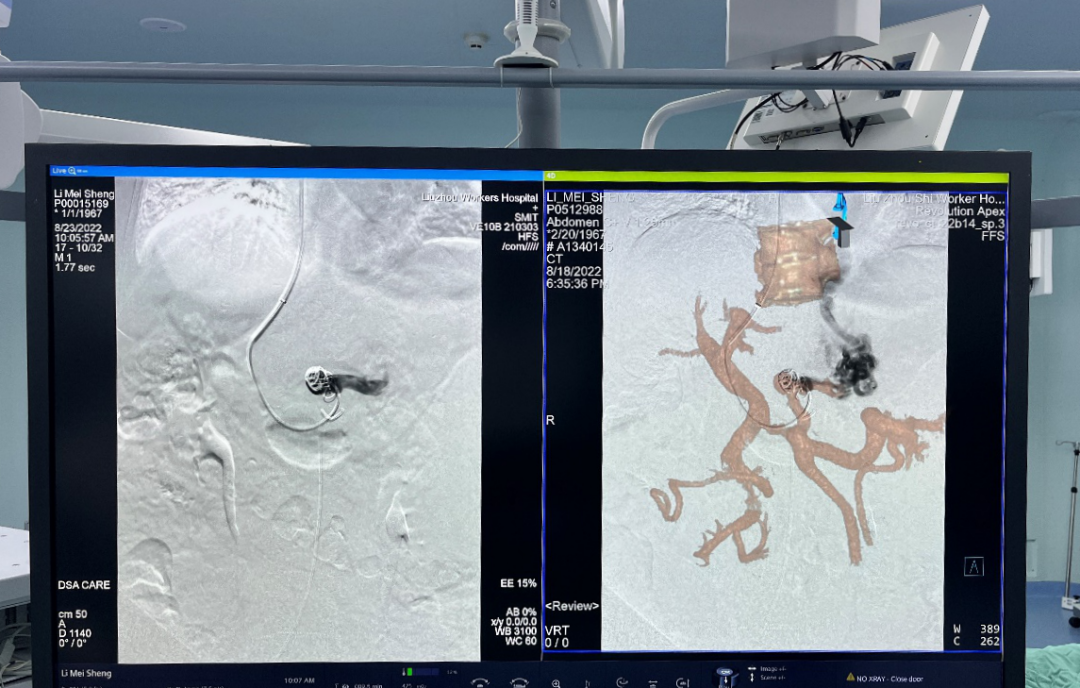

术中的3D融合影像

术中显示屏中实时引导的3D融合影像